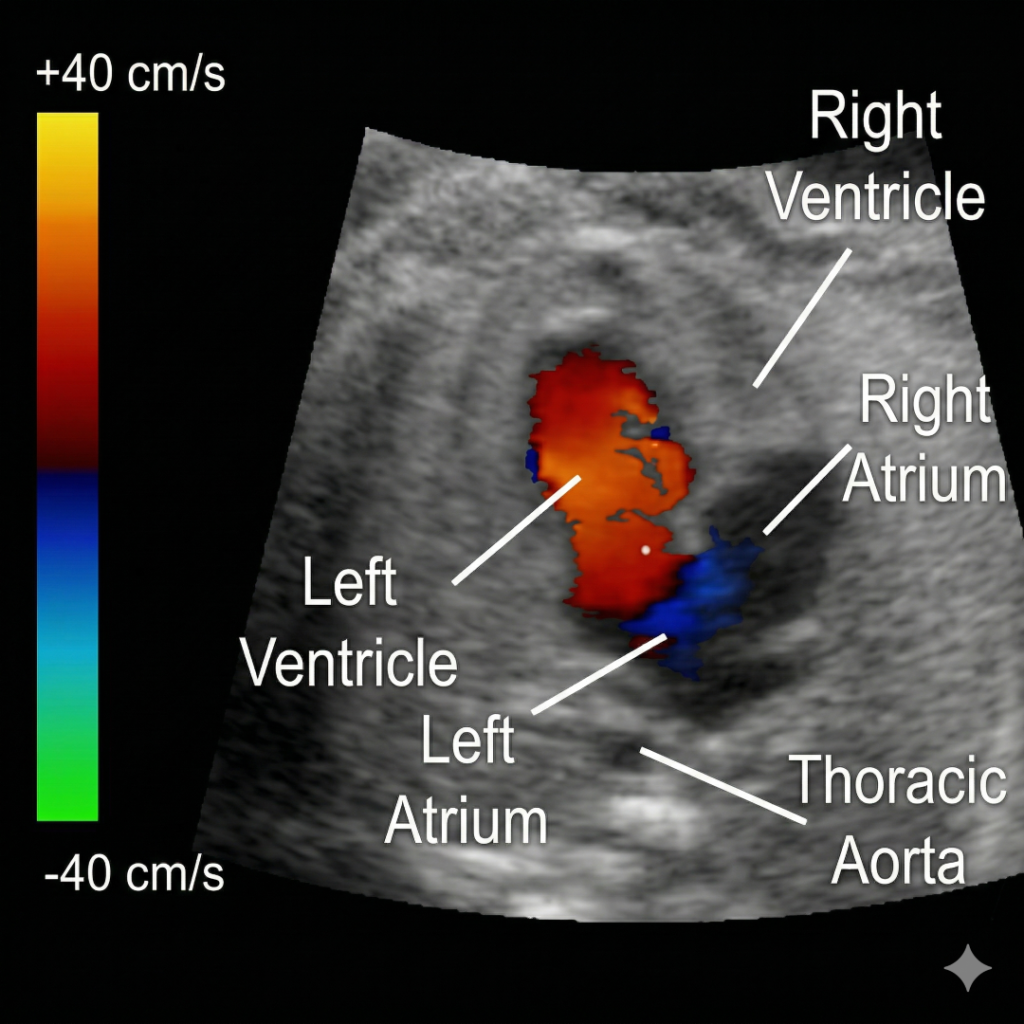

Doppler Ultrasound

Assess Blood Flow with Doppler Ultrasound

A Doppler ultrasound uses sound waves to check blood flow in your arteries and vessels. It helps detect narrowing or blockage that may increase the risk of heart attack or stroke.

Echocardiogram (Echo)

An ultrasound scan of your heart that shows how well your heart and valves are functioning, and detects structural problems.

A special ultrasound that checks blood flow in your heart and major arteries, helping to spot blockages or narrowing of blood vessels.